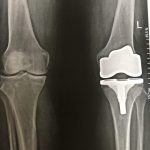

تعویض مفصل زانو و لگن

– ساییدگی مفاصل

– از بین رفتن مفاصل